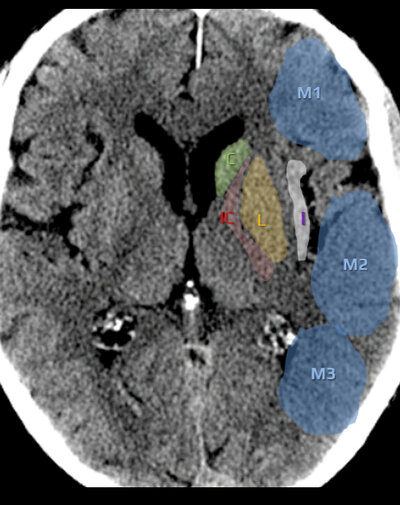

Coupe des ganglions de la base

ASPECTS — Coupe ganglions de la base : C, L, IC, I, M1, M2, M3

C = caudé · L = lenticulaire · IC = capsule interne · I = insula · M1-M3 = cortex ACM